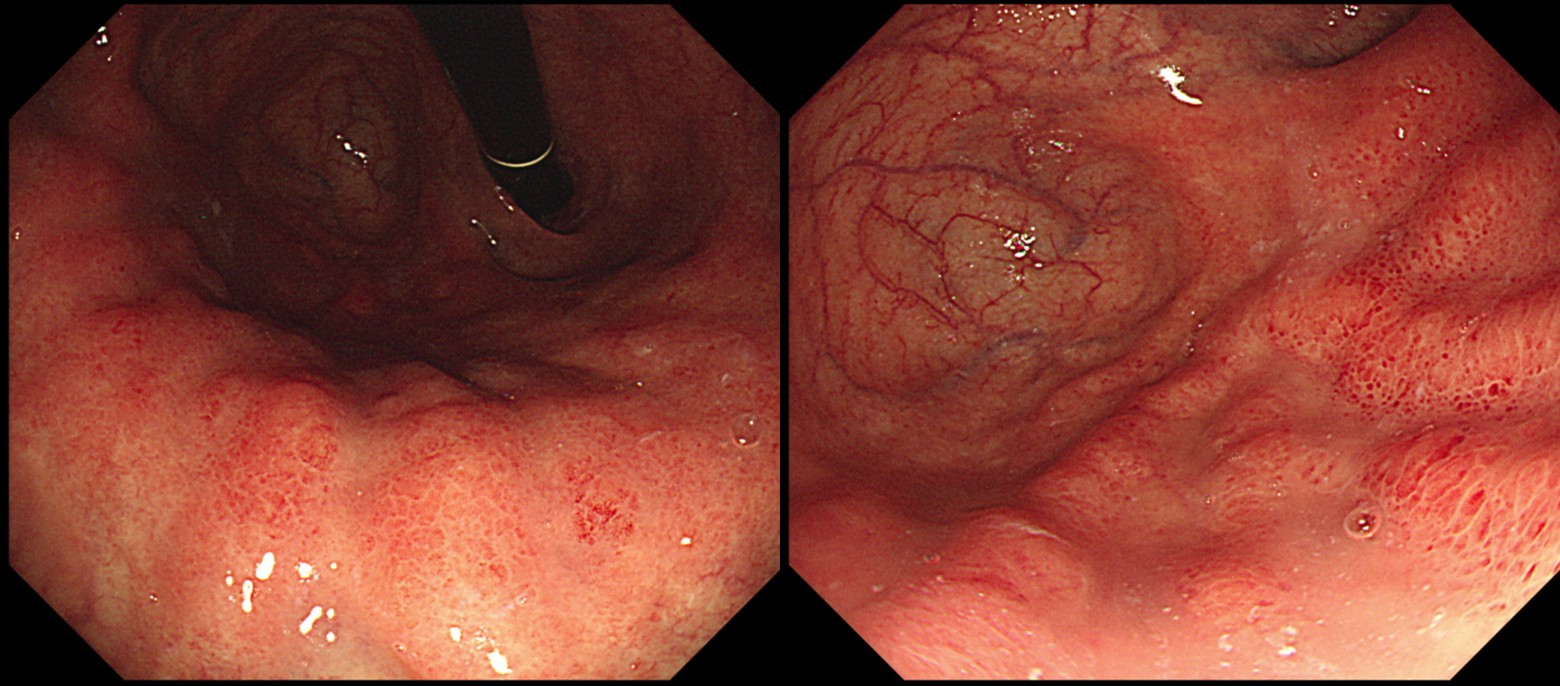

[Gastric cancer (EndoTODAY gastric cancer 968)]

Autoimmune gastritis is one of risk factors for gastric cancer especially in Helicobacter negative individuals. In this old lady, a typical B4 cancer was seen at high body greater curvature. But the background gastric mucosa was very atrophic.

Blood tests were severe atrophy with PCA (+) and Hp serology (equivocal).

Total gastrectomy was done.